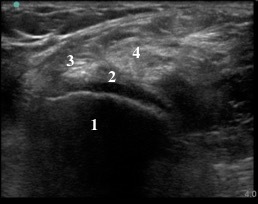

1. Medial Femoral Condyle

2. Articular Cartilage

3. Semi-membranosus Tendon

4. Medial Head of the Gastrocnemius